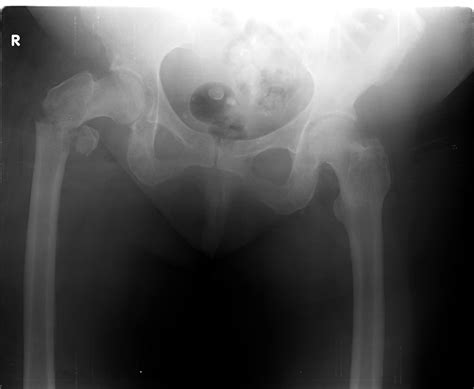

Xray Of Bone Fracture

Bone fractures are a common injury that can occur due to various reasons such as accidents, falls, or sports injuries. An accurate diagnosis is crucial for effective treatment, and one of the most reliable methods for diagnosing bone fractures is through an X-ray of bone fracture. This non-invasive imaging technique provides detailed images of the bones, helping healthcare professionals to assess the extent of the damage and plan appropriate treatment.

An X-ray of bone fracture is a critical diagnostic tool that provides a clear view of the bone structure. This imaging technique uses electromagnetic radiation to produce images of the inside of the body. When it comes to diagnosing bone fractures, X-rays are particularly useful because:

Interpreting X-ray images requires specialized training and expertise. Radiologists look for several key indicators when assessing an X-ray of bone fracture:

• Bone Alignment: They check if the bone fragments are properly aligned or if there is any displacement.

• Fracture Pattern: They identify the type of fracture (e.g., transverse, oblique, spiral) to understand the mechanism of injury.

• Bone Density: They assess the density of the bone to detect any signs of osteoporosis or other bone diseases.

• Soft Tissue Injuries: They look for any associated soft tissue injuries, such as swelling or muscle damage.